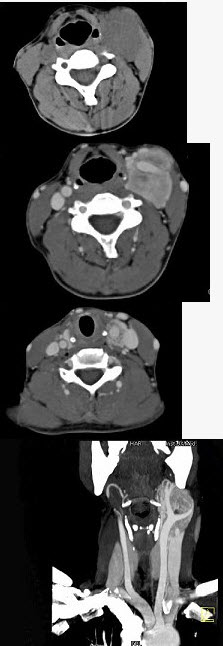

女,39岁,左颈部可扪及一肿块,无发热,无疼痛,CT如图所示,最可能的诊断是()。

A、颈部神经鞘瘤

B、颈动脉体瘤

C、颈部神经纤维瘤

D、颈部海绵状血管瘤

E、颈动脉瘤

正确答案:

B